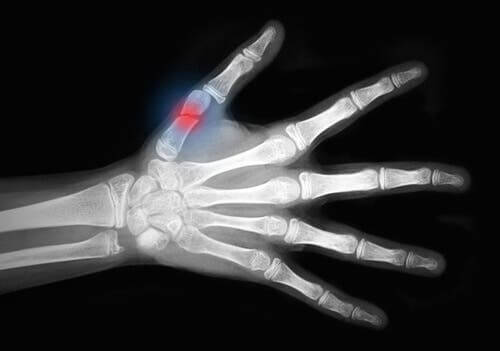

Dans le milieu de la médecine, les lésions traumatiques qui arrachent les tissus mous de la peau dans des zones étendues et laissent à la vue l’os s’appellent « lésions de dégantage ». En général, celles-ci affectent les extrémités.